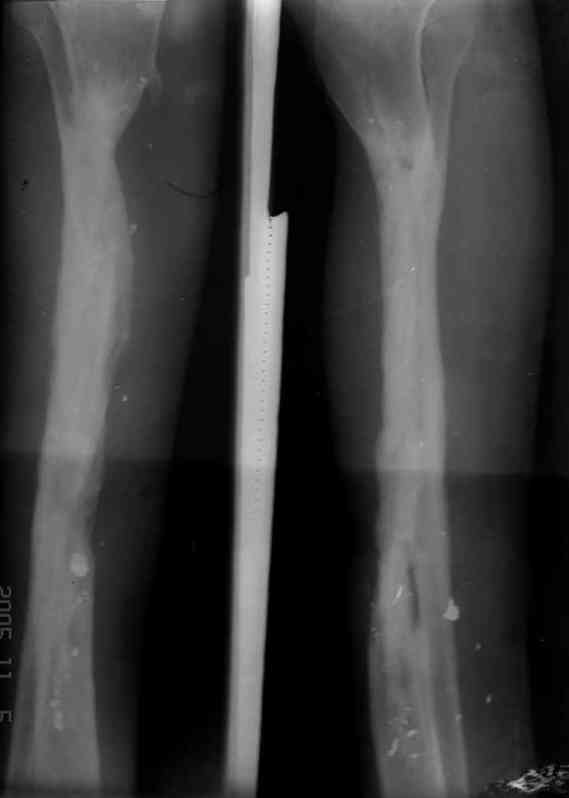

Реализовал описанную выше методику, и в итоге вот что получилось. Высылаю лишь прямые проекции,

в боковых тоже всё в тему.

Сейчас аппарат сняли, но случай ещё не завершенный.

Признаюсь честно, не совсем уверен в прочности консолидации на стыке косточек. Кроме того, укорочение в районе 6 см. Сейчас реабилитация - ходит опираясь на ногу с одним костылем.

Продолжение, видимо, будет... Возможно, будем удлинять.